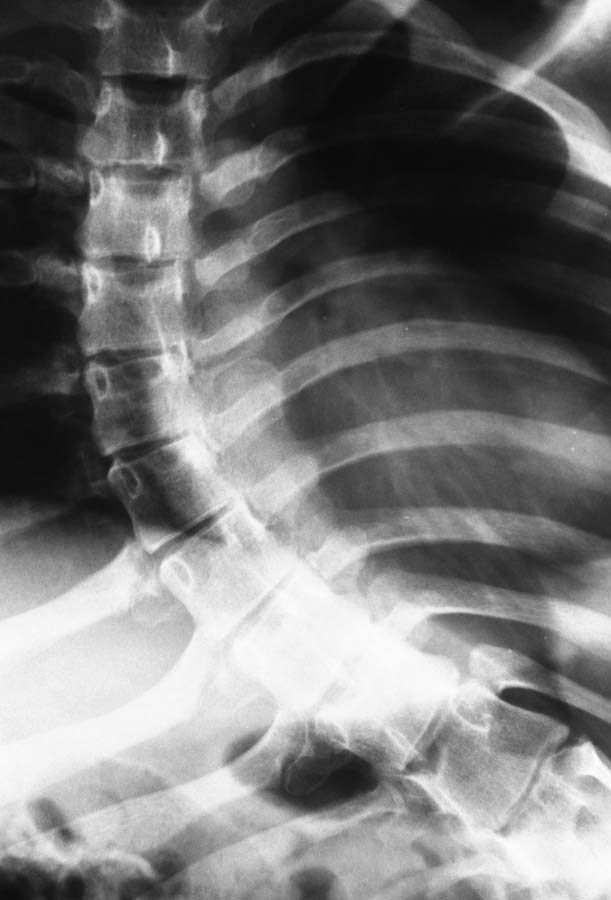

ДЦП, Сколиоз и вывих бедра.

Пациентка 1992 г.р. Болеет ДЦП с рождения. до 2005 г. наблюдалась у неврологов , ходила с поддержкой. В 2005 г. перелом средней трети бедра. Лечилась консервативно в больнице Краснодара.

После лечения постепенно стало наростать укорочение конечности и искривление позвоночника.На представленных Р-гр состояние на сегодняшний день.больная занимает вынужденное полулежачее состояние.Вопрос - где нибудь на просторах РФ могут помочь?????